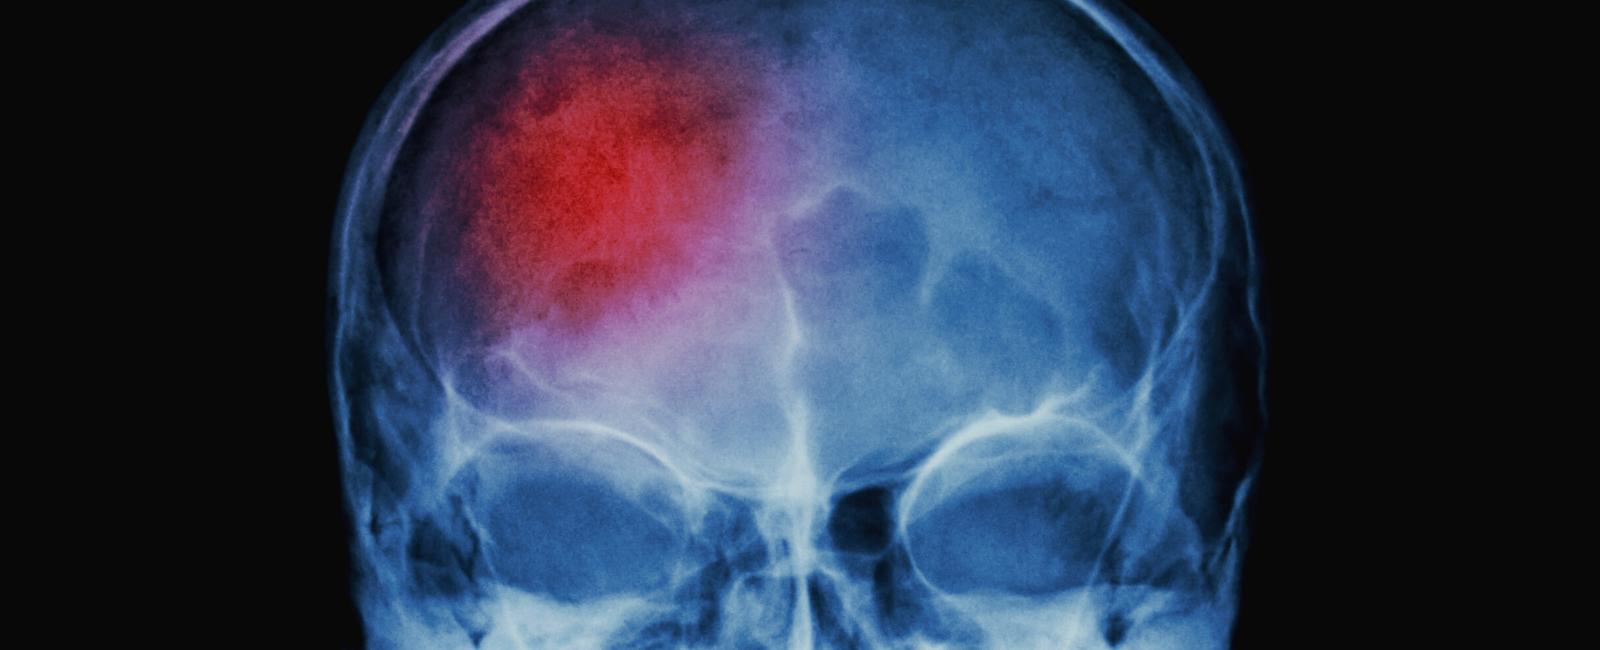

Cerebral ischemia is a brain stroke caused by a blocked artery that supplies blood to the brain. Subarachnoid hemorrhage is bleeding in the space surrounding the brain and is often due to a blood vessel that bursts and leaks, a condition called aneurysm.

Aneurysmal subarachnoid hemorrhage (SAH) is a serious condition that often leads to death. Half of all patients die, and one out of every five survivors is left dependent on others. If a patient survives the initial hours after SAH and receives early treatment for the aneurysm, they are at risk for delayed cerebral ischemia (DCI). This situation occurs in about one-third of patients and usually happens between four and ten days after SAH.